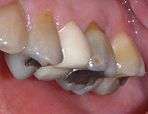

Temporary crown

A temporary crown (white) on a tooth after Endodontic therapy

A temporary crown (provisional crown, interim crown) is a temporary (short-term) crown used in dentistry. Like other interim restorations, it serves until a final (definitive) restoration can be inserted. Usually the temporary crown is constructed from a chemical-cure composite, although alternative systems using aluminium crown forms are occasionally used.[1] Temporary crowns function to protect the tooth, prevent teeth shifting, provide cosmetics, shape the gum tissue properly, and prevent sensitivity.[2]